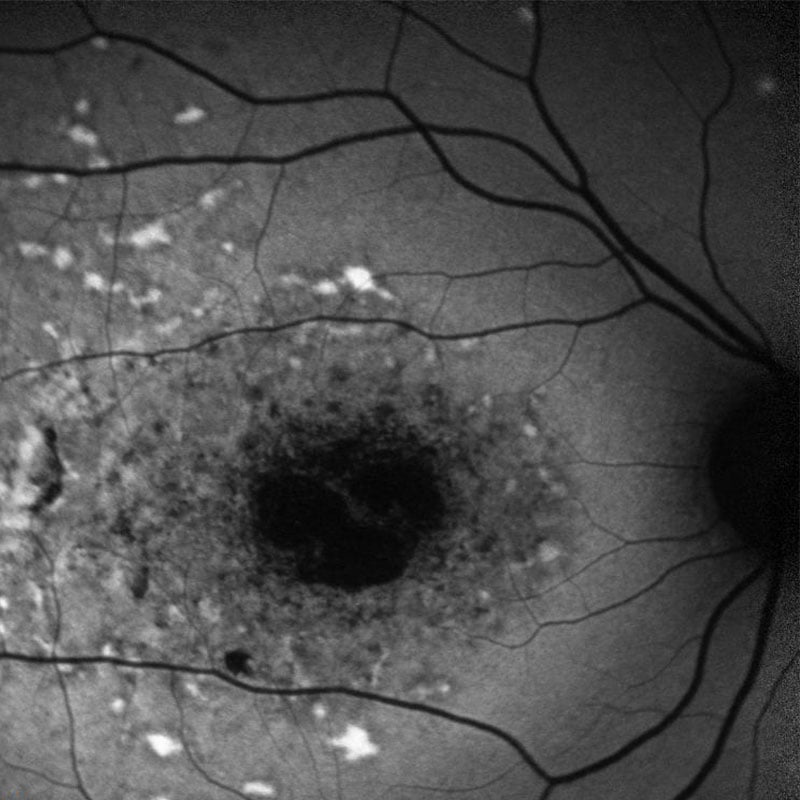

Πρόκειται για την πιο συχνή δυστροφία Ωχράς της νεανικής ηλικίας. Συνήθως οι ασθενείς (παιδιά, νέοι) δυσκολεύονται στην κεντρική όραση και κυρίως στην ανάγνωση. Η νόσος STARGARDT έχει πολύ μεγάλη ποικιλία στην εμφάνιση και την πρόγνωση γι’ αυτό και ο κάθε ασθενής πρέπει να αντιμετωπίζεται εξατομικευμένα από εξειδικευμένη ομάδα επιστημόνων προκειμένου να λάβει σωστή κλινική διάγνωση, παρακολούθηση, αντιμετώπιση, γενετική διάγνωση και συμβουλευτική.